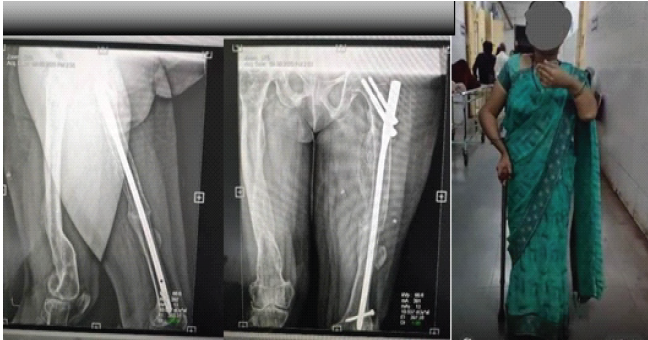

A 34-year-old female with known type ⅠA OI was admitted to our emergency department for a spontaneous left midshaft femur fracture on weight-bearing. She had a history of an atypical left femur fracture 1 month back, for which she was managed conservatively on oral medications. She also reported that she had a right femur fracture at 18 months of age while massaging, then had B/L upper limb forearm fractures while playing at around 8–10 years, all managed conservatively. The patient is of short stature with 1.30 m (Figs. 1 and 2).

Figure 1: X-rays of right atypical right femur fracture, which was managed conservatively.

Figure 2: Pre-operative X-rays and clinical photos of the upper limb and lower limbs.

Patient pre-anesthetic evaluation workup was done and posted for surgery. The patient was placed supine on a fracture table, after standard painting and draping, and slight traction was applied. Moreover, closed reduction of the fracture was attempted and achieved under C-arm guidance. A small lateral incision was made proximal to the greater trochanter. An entry point was made at the tip of the greater trochanter under image guidance, and a guidewire was passed through the proximal femur into the shaft. Reaming was done over the guidewire sequentially. A long proximal femoral nail (PFN) (length: 28 cm, diameter: 9 mm) was inserted over the guidewire. Fracture alignment was confirmed under C-arm. 8 mm and 6 mm proximal locking screws were inserted through the jig. Distal locking was done using the freehand technique under C-Arm. Final fluoroscopy confirmed satisfactory fracture reduction, implant position, and screw placement. The wound was irrigated with saline, and hemostasis was ensured. Wound closure was done in layers. A sterile dressing was applied. The post-operative patient was allowed toe-touch with a Zimmer walking frame. Clinical and radiographic follow-up showed no displacement and consolidation after 8 weeks, and hence, full weight-bearing was started as tolerated. The patient was followed up after 5 months, and her physical status was almost comparable to the pre-operative level without any complications (Fig. 3, 4, 5, 6).

Figure 3: Immediate post-operative X-rays.

Figure 4: Partial-weight bearing X-rays after 2 weeks.

Figure 5: Partial weight-bearing X-ray after 3 months.

Figure 6: Full weight bearing after 5 months.